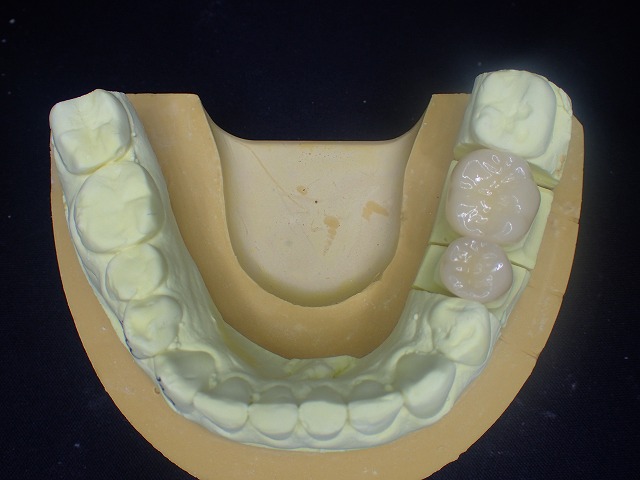

まずは下顎から診査

インビサラインのマウスピースが入っています。

この状態で奥歯をジルコニアに交換するのは

難題です。

かぶせ物を交換した場合には

この維持装置が使えなくなる場合があるので

維持装置を作り直す必要の可能性があります。

左下

プラスチック冠 おそらくcad/cam冠

かもしれません。

歯と歯はお互いに接触しなくてはなりません。

「コンタクト」と言って歯科では重要視される

状態で、適切なコンタクトが歯周病や虫歯、

咬み合わせなどに関与しています。

右下

同じくコンタクトしていません。

cad/cam冠はすぐに減るので

お口の中を大切に思いう人は、入れないほうが

良いと思います。

左側のcad/cam冠をジルコニアクラウンに交換

激しい歯ぎしりでCAD/CAM冠が

大きく摩耗しています。

そのため歯と歯の間に隙間ができています。

ジルコニアクラウンに交換

左側のCAD/CAM冠を除去してジルコニアを制作

cad/cam冠などのプラスチック関係の

かぶせ物は、歯肉に炎症を起こす場合がほとんどです。

両側の摩耗したCAD/CAM冠を

ジルコニアクラウンに交換できました。